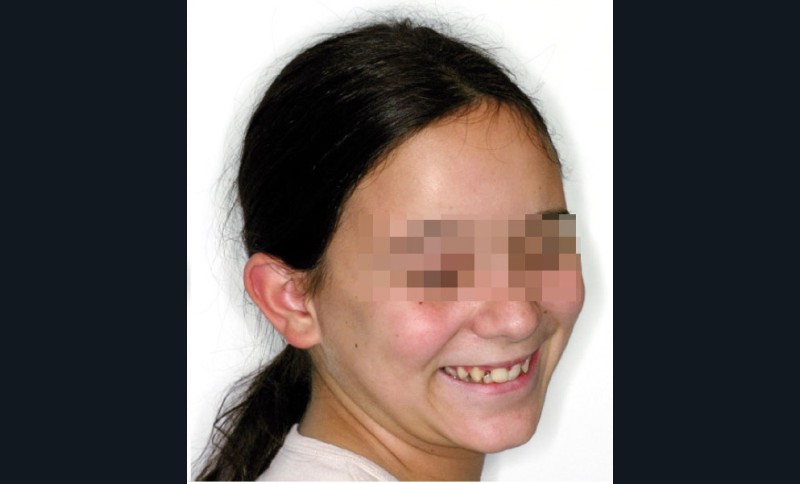

Ludivine T. âgée de 12 ans et demi présente une agénésie des deux incisives latérales maxillaires dans un contexte occlusal de classe II division 2 (fig. 1 à 3).

L’examen clinique exo-buccal révèle un visage équilibré en classe I squelettique tendance hypodivergente. De profil, le menton est marqué et le profil sous nasal très légèrement concave (fig. 1).

Les photographies de fin de traitement (fig. 4 et 5) montrent la préservation de l’équilibre facial et le respect du profil sous-nasal qui, malgré la croissance, ne s’est pas creusé. Le sourire est très harmonieux et révèle, comme les photographies endo-buccales, la très bonne intégration des canines substituées, après légère coronoplastie de leur pointe.